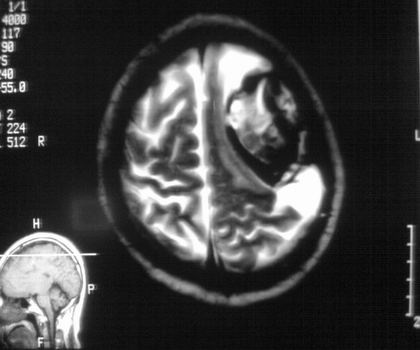

以下是引用影像孺子牛在2008-4-29 21:20:00的发言:[br]首先病变定位在脑外,根据ct密度及mri信号特征考虑慢性硬膜下血肿不连续环形钙化。

以下是引用周战梅在2008-4-29 23:12:00的发言:[br]脑外病变,蛛网膜下腔增宽,囊壁点状、环形钙化,增强扫描呈不均匀环状强化,考虑为囊性脑膜瘤可能性大,慢性脓肿、血肿机化、胆脂瘤不能除外。